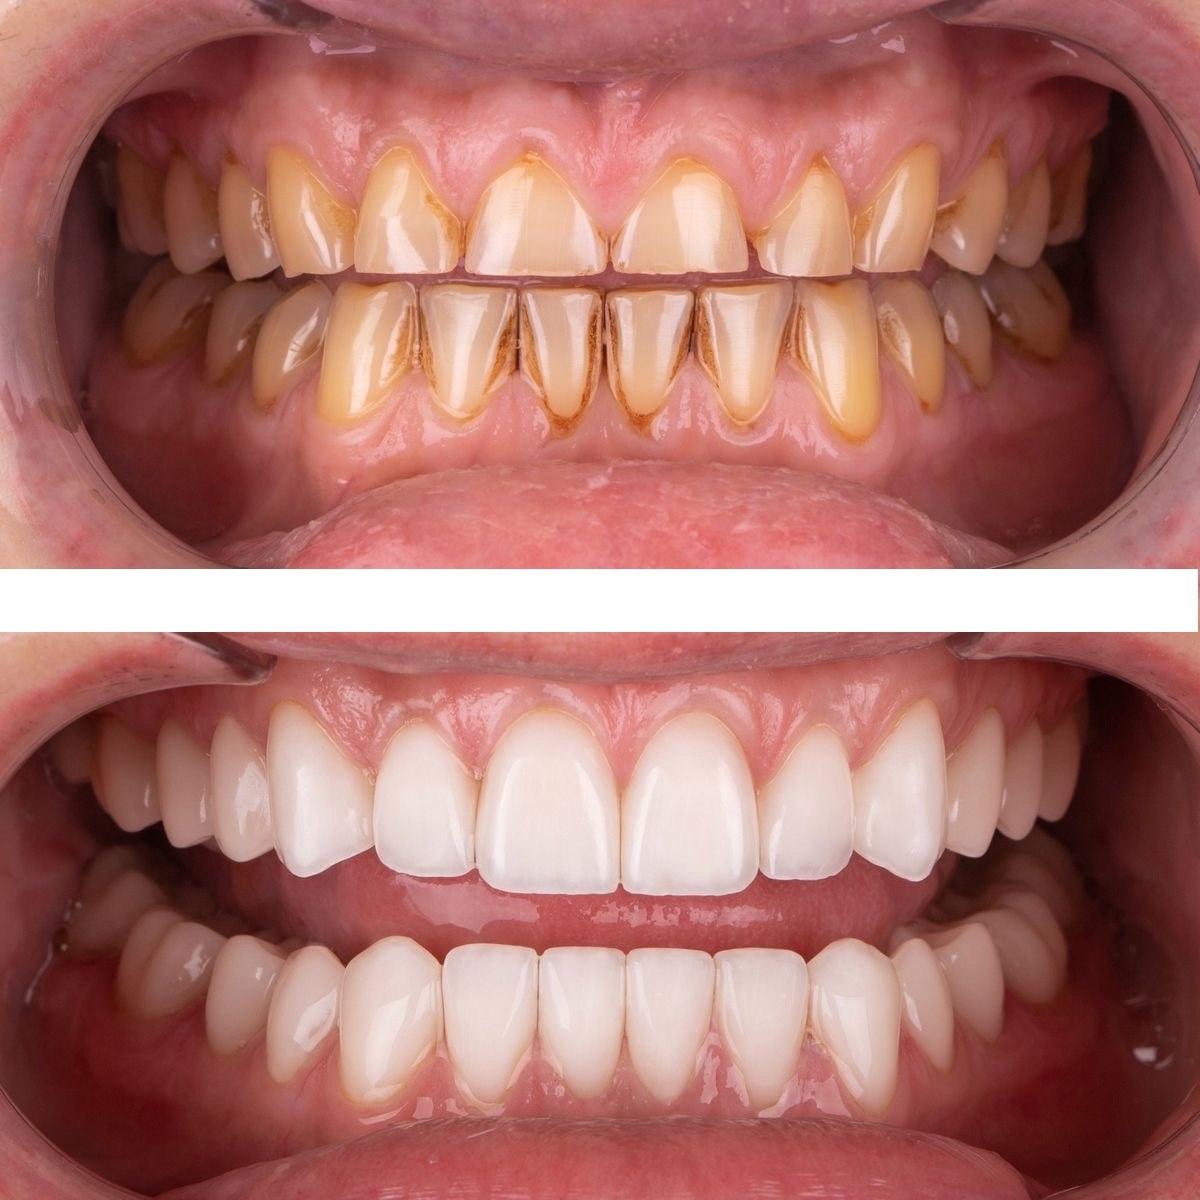

/ 5

В стоматологическом центре “5 Принципов” в Симферополе мы предлагаем качественное протезирование, которое возвращает не только полноценную функцию зубного ряда, но и уверенную улыбку. Наши специалисты подбирают индивидуальные решения под каждого пациента: затемнение участка, восстановление зубов, подбор материалов и форм, максимально близких к природной эмалированной структуре. Мы уделяем особое внимание деталям: точная примерка, правильная окклюзия и гармония с соседними зубами. В арсенале клиники современные технологии — CAD/CAM системами мы проектируем протезы на основе цифровых снимков, что обеспечивает точность посадки и ускоряет сроки изготовления. Виды протезирования, которыми мы гордимся, включают металлокерамические и керамические коронки, мосты и частичные съемные протезы, а также имплантаты в сочетании с фиксированными конструкциями. В “5 Принципах” акцент ставится на функциональность, эстетику и долговечность. Мы тратим время на тщательную консультацию: обсуждаем форму, цвет и стиль улыбки, чтобы результат гармонировал с лицом и возрастом пациента. Используем биосовместимые материалы, снижаем риск аллергических реакций и повышаем комфорт. Пациенты в Симферополе доверяют нам, потому что видят естественную улыбку, улучшение жевательной функции и уверенность в себе. Запишитесь на консультацию и убедитесь, как протезирование в нашем центре может изменить вашу улыбку к лучшему.